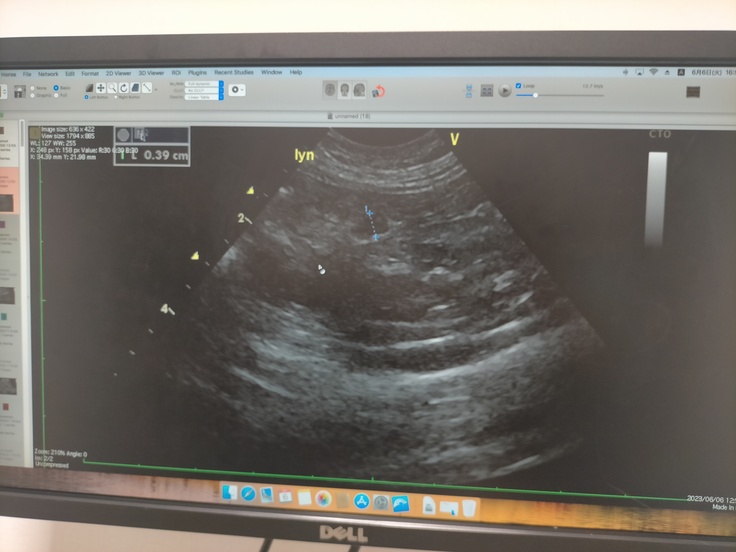

エコー検査でマーカーがついている部分はリンパ節ですが、0.3mmなので、平均内とのことでOKです🙆🏻